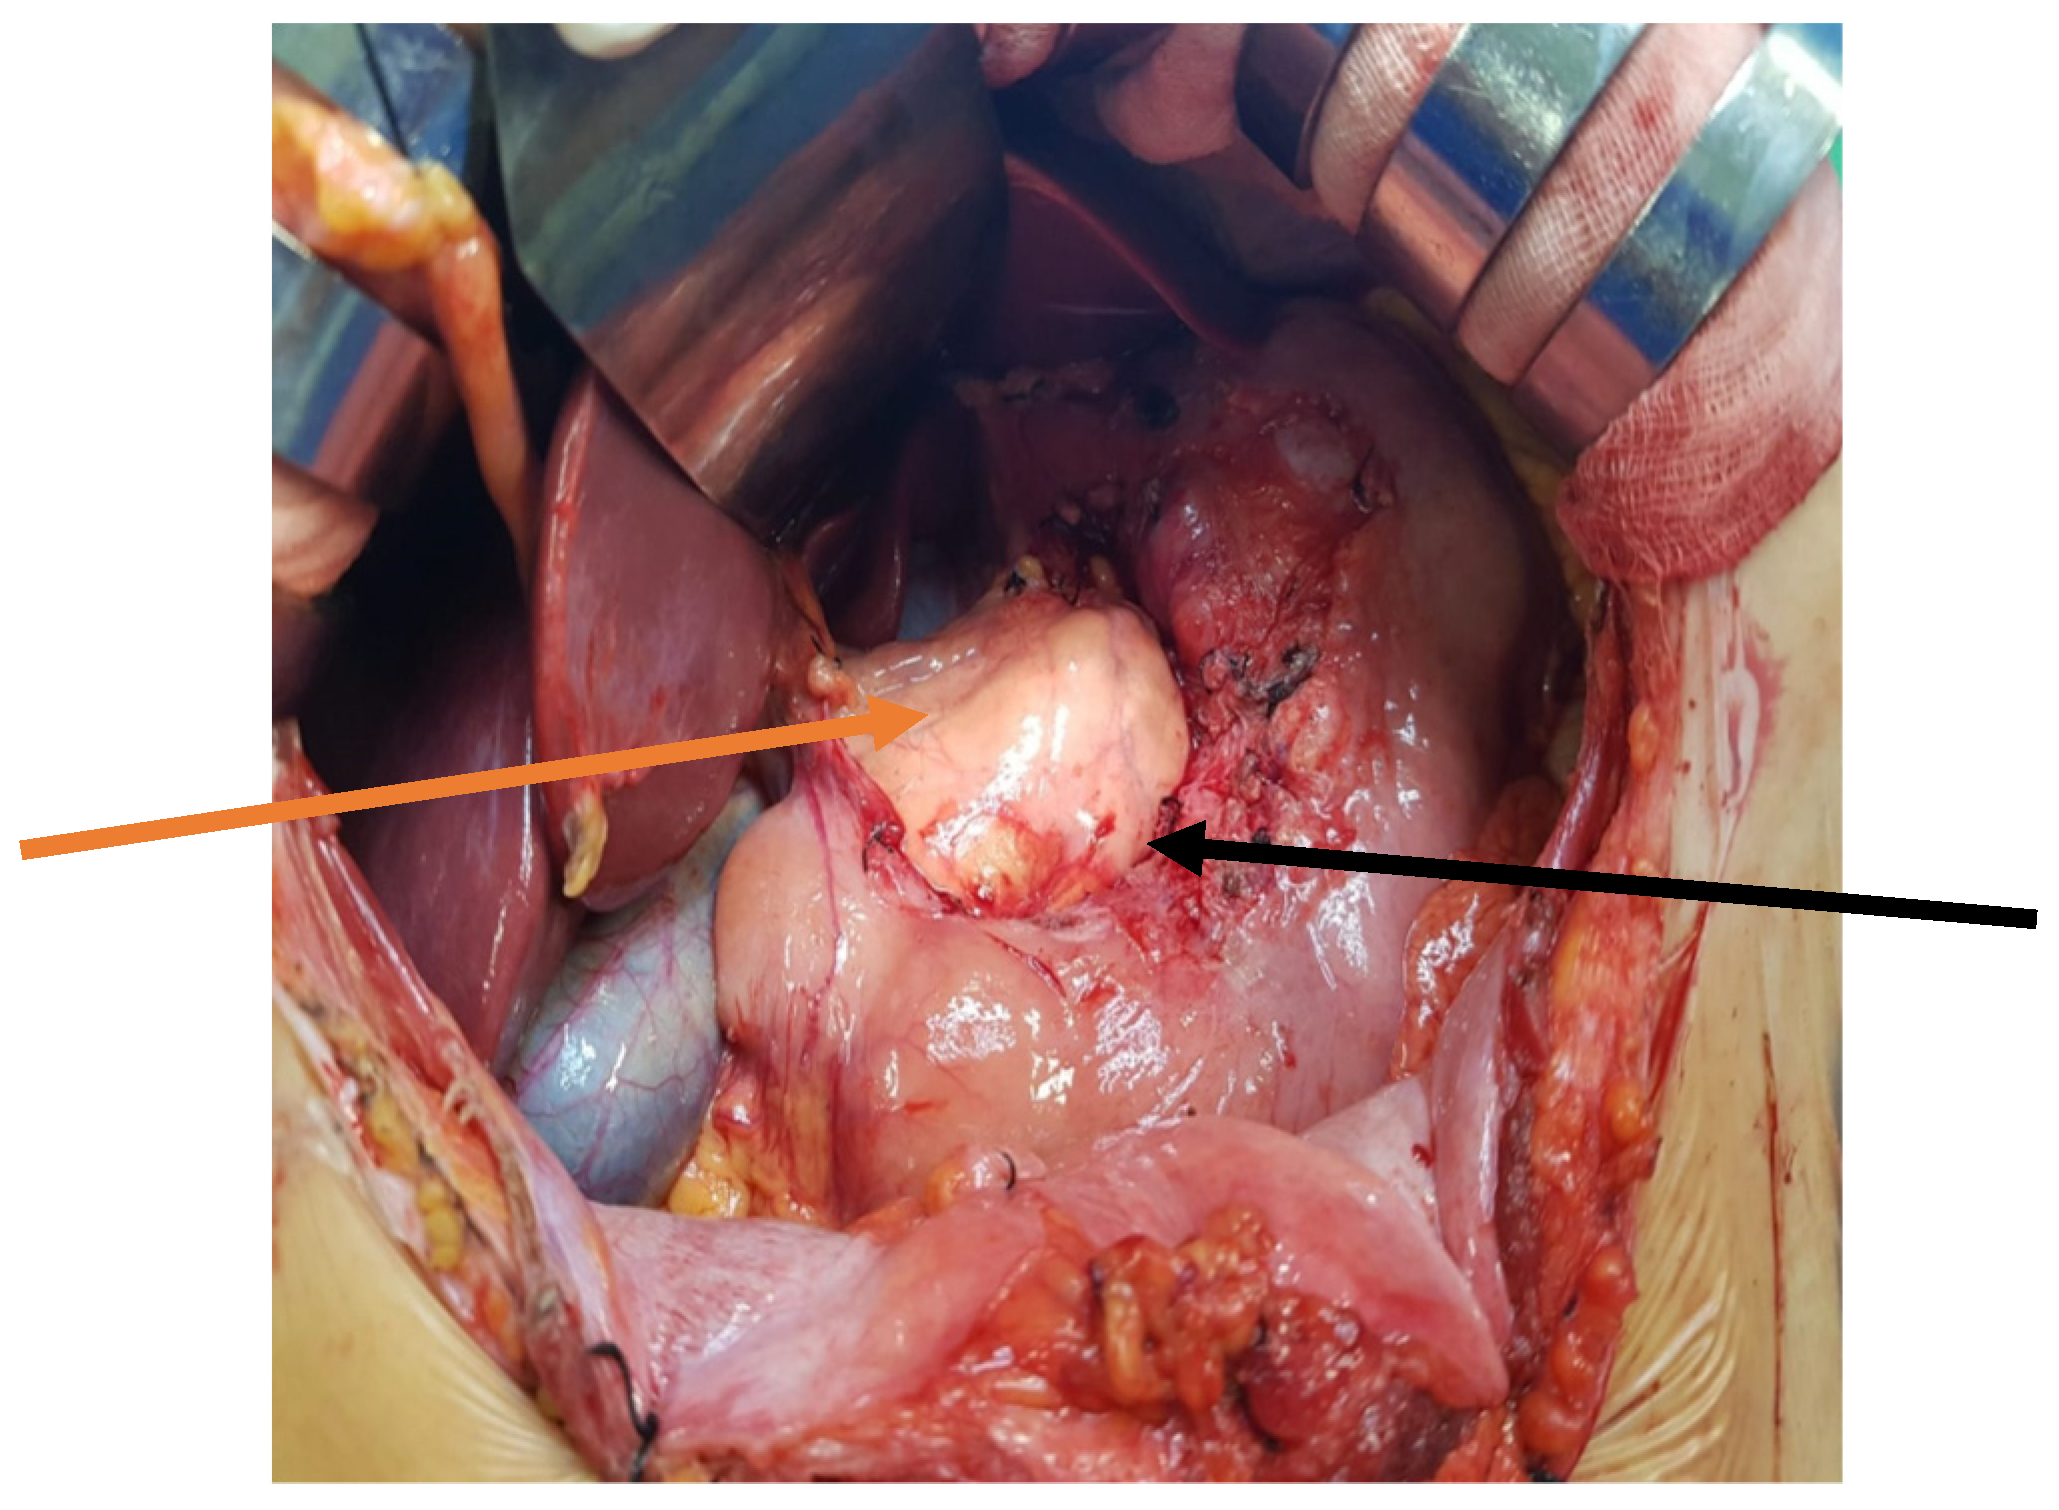

The patient was qualified for elective surgery. The presence of an approximately seven-cm long soft tissue extending along the lesser curvature of the stomach, closely connected to the stomach wall, was found intraoperatively (Figure 2). The tumour penetrated the gastrohepatic ligament, but did not reach the liver. The lesion did not penetrate the retroperitoneal space or infiltrate the pancreas. The tumour was completely removed without gastric wall resection (Figure 3). After removal of the lesion, the serosa of the lesser curvature of the stomach was secured with a continuous PDS 4/0 suture (Figure 4).

Figure 2. Intraoperative image—The tumour was close to the lesser curvature of the stomach. The arrows indicate: the lesser curvature of the stomach (red arrow), and the anterior surface of the tumour (black arrow).